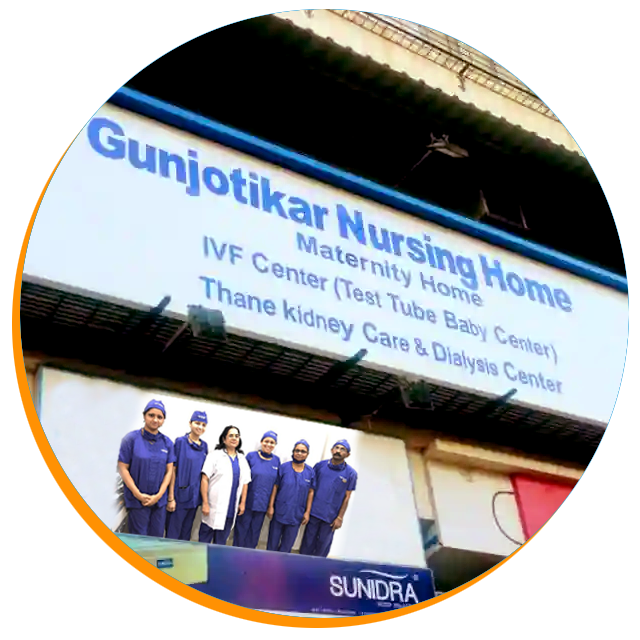

Dr. Sushma Gunjotikar

M.B.B.S., D.A. (BOM), D.N.B. (OBGY)

Obstetrician, Gynecologist & Infertility Specialist Endoscopist

Dr. Sushma Gunjotikar (Gunjotikar Hospital) in Mumbai treats the various ailments of the patients by helping them undergo high-quality treatments and procedures. Among the numerous services offered here, the clinic provides treatments for Uterine Fibroids or Myomas, Ovarian Cysts, Endometriosis, Pelvic Organ Prolapse, Urinary Problems, Vaginal Discharge, Subfertility, Menopause, Gynaecological Cancers, Abnormal Pap Smears - Pre-Invasive Cervical/Vaginal Disease and Vulva Conditions. The doctor is also listed under Gynaecologist & Obstetrician Doctors. Furthermore, the patients also visit the clinic for Contraception Advice, HPV Tests, and Biopsy Tests etc. The doctor is one of the leading infertility specialists in the area.